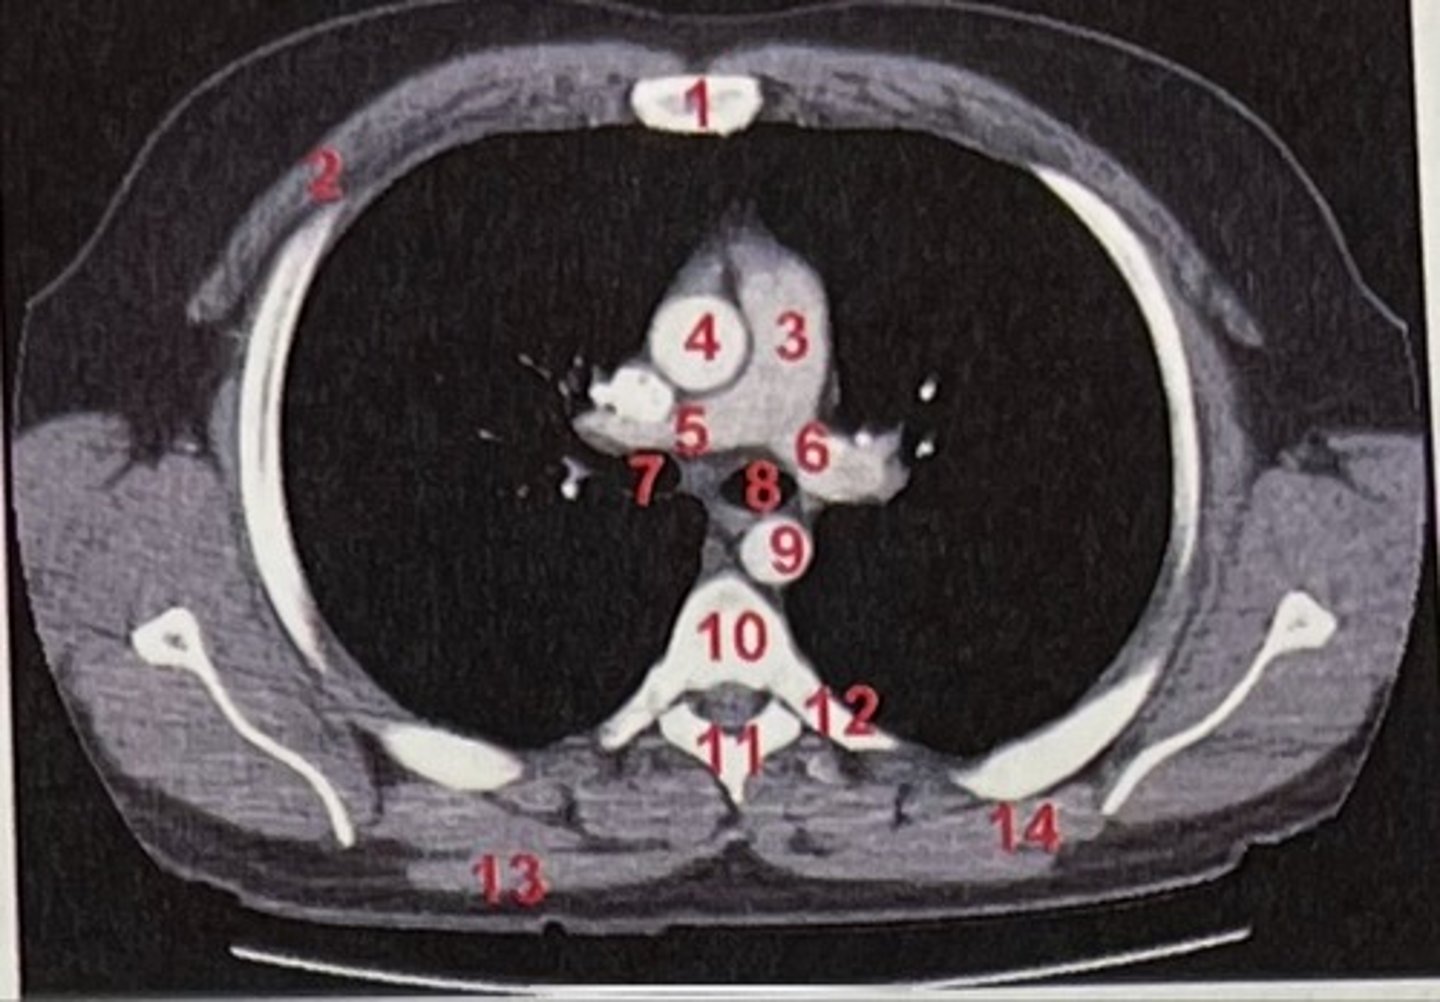

Sternum

What is 1

pectoralis major

What is 2

Pulmonary trunk

What is 3

Right and left pulmonary arteries

What is 5 and 6

Ascending aorta

What is 4

right primary bronchus, left primary bronchus

What is 7 and 8

Descending aorta

What is 9

Rhomboid major

What is 14